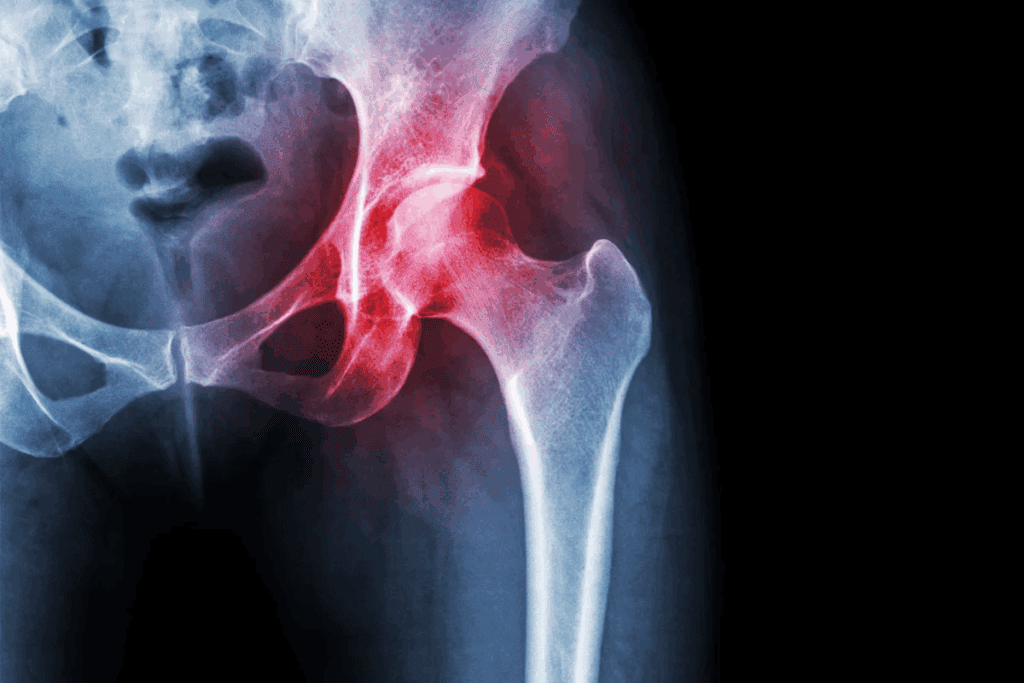

Osteoporosis is called a “silent disease” because it quietly weakens bones. It happens without symptoms until a bone breaks. It affects bone density, making bones more likely to break.

Osteopenia and osteoporosis both have low bone mass. But osteopenia is less severe. Osteoporosis means bone density is much lower, raising the risk of breaks.

Early diagnosis through bone density tests is key. It helps tell osteopenia from osteoporosis. This allows for early action to stop bone breaks.